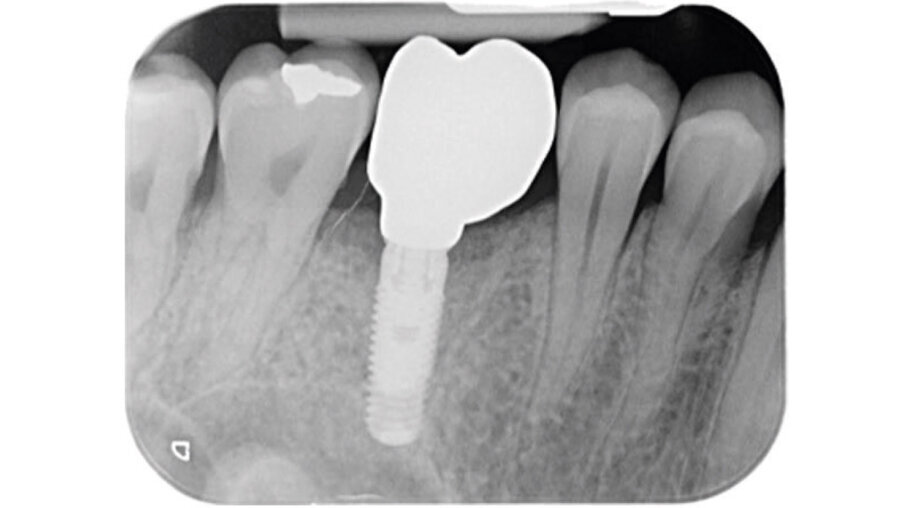

Dopo l’esecuzione dell’anestesia locale, il dente è stato rimosso e l’alveolo pulito dai residui del legamento parodontale. È stato inserito l’impianto (Zimmer TSV, Zimmer, Parsippany) 4.1 x 11,5 TSVM posizionato seguendo il protocollo consigliato dal produttore (Fig. 3). L’impianto è stato inserito a livello della cresta alveolare. È stato avvitato lo scan-abutment (Zfx Intrascan Matchholder, Zfx,). È stata rilevata un’impronta ottica intra-operatoria dell’emiarcata in cui è stato posizionato l’impianto con lo scan abutment (Fig. 3). Il gap tra l’osso vestibolare e l’impianto è stato riempito con Bio-Oss (Geistlich Pharma) (Fig. 4). Al termine della chirurgia è stato progettato e fresato il provvisorio, che è stato applicato appena pronto, dopo aver inserito la matrice in collagene volumetricamente stabile Fibro-Gide (Geistlich Pharma) precedentemente imbibita con il gel a base di polinucleotidi e acido ialuronico Regenfast (Officine Bio-Farmaceutiche Mastelli), al di sotto della vite stessa (Figg. 5, 6). Data l’accuratezza della vite non sono state necessarie suture. Al termine della procedura è stata eseguita una radiografia di controllo (Fig. 7).

Fig. 7 - Radiografia di controllo dopo il posizionamento della vite di guarigione customizzata.